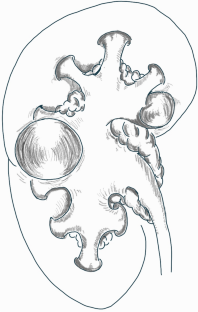

Simple renal cysts are a common finding during abdominal imaging assessment. The incidence increases with age and it is higher in male gender. Parapelvic cysts are a subset of simple cysts that arise within the renal parenchyma, adjacent to the renal sinus, characterized by being generally single, larger, and incompletely surrounded by renal parenchyma. Noteworthy, parapelvic cysts are a rare and understudied condition which, although considered clinically insignificant due to the absence of influence on renal function, still have a controversial aetiopathogenesis. On the other hand, urological management and differential diagnosis have been thoroughly investigated. The aim of our review is to provide an overall vision on this rare condition, usually misdiagnosed and underestimated, on the basis of more recent data. An accurate differential diagnosis of parapelvic cysts can lead to the identification of treatable conditions such as Fabry disease, autosomal dominant polycystic kidney disease, polycystic liver disease and tuberous sclerosis complex disease.